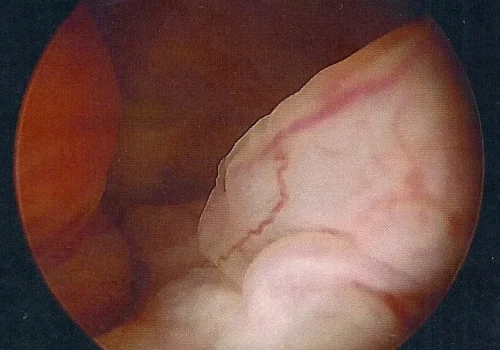

Hysteroscopy – Polypectomy

Procedure

A Hysteroscopy revealed 3 large endometrial polyps which were removed.